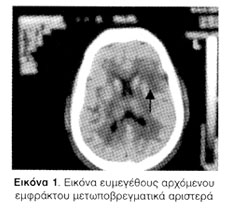

Στην αξονική τομογραφία εγκεφάλου περιγράφηκε αρχόμενο ευμέγεθες έμφρακτο μετωπο-βρεγματικά αριστερά, παλαιές ισχαιμικές βλάβες στα βασικά γάγγλια αριστερά, κροταφικά και βρεγματικά δεξιά και σχετική εκσήμανση των υπαραχνοειδών χώρων του εγκεφάλου (Εικόνα 1).